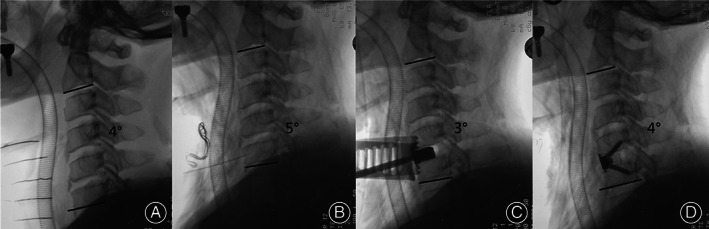

Fig. 5.

The intraoperative radiograph of a 55‐year‐old man who underwent anterior cervical discectomy and fusion at C5‐6 level employing traditional neck pillow (TNP). The radiograph showed C2‐C7 lordosis (CL) was 4° at the beginning of the surgery (A). When decompression steps were accomplished, the intraoperative radiograph showed CL was 5° (B). For TNP group, the neck posture was settled before surgery and remained unchanged (C). When Zero‐P was inserted, the CL suffered a tiny remained at 4° (D).